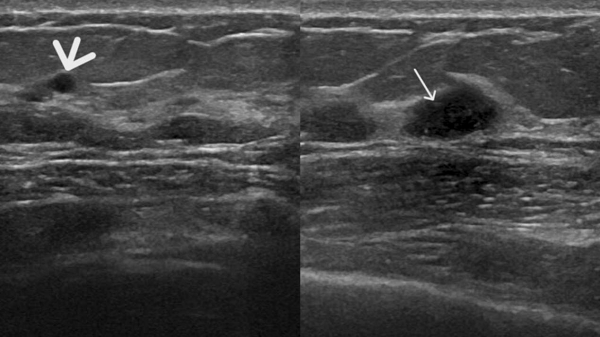

患者A钼靶显示“正常”,但超声发现囊肿和实性结节(如图1、2);

图2 患者A的超声表现图:(粗箭头处)乳腺囊肿,表现为无回声区;(细箭头处)乳腺实性结节,表现为低回声